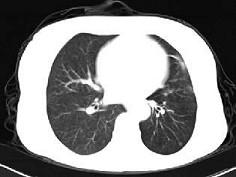

男,45岁,外伤后行CT检查如图,最可能的诊断为 ( )A、肺大疱B、支气管囊肿并感染C、左主支气管断裂D、畸胎瘤E、支气管肺炎

问题 男,45岁,外伤后行CT检查如图,最可能的诊断为 ( )

选项 A、肺大疱 B、支气管囊肿并感染 C、左主支气管断裂 D、畸胎瘤 E、支气管肺炎

答案 C